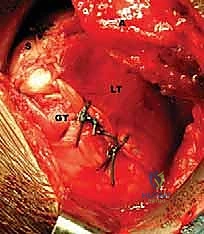

FIG 4 • C. The latissimus dorsi tendon is released from its humeral insertion.

FIG 4 • D. The thoracodorsal neurovascular pedicle (TD) is identified and protected.